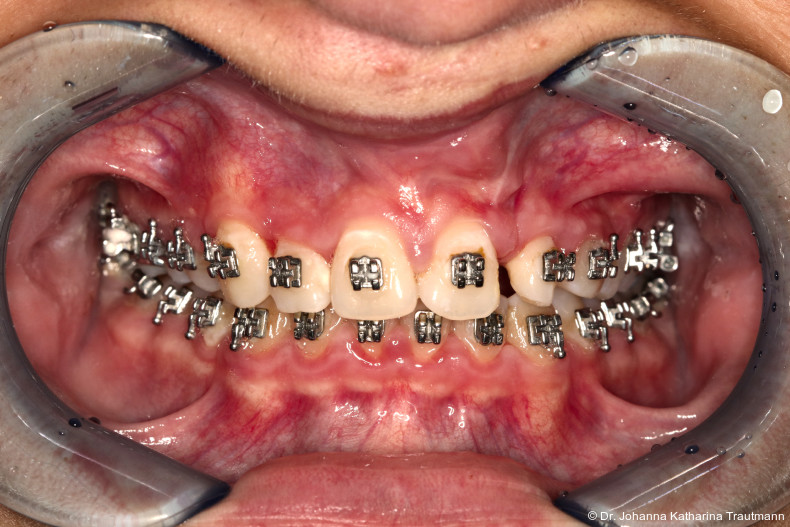

Nach etwa zwei Jahren initialer Behandlung konnte nach abgeschlossenem Wurzelwachstum aller bleibenden Zähne (mit Ausnahme der Weisheitszähne) mit der Hauptbehandlung unter Verwendung einer vollständigen Multibracketapparatur von 7 bis 7 im Ober und Unterkiefer begonnen werden. Die vergleichsweise lange Vorbehandlung erscheint zwar auf den ersten Blick behandlungszeitverlängernd, sorgt jedoch für eine deutlich bessere Mundhygienefähigkeit sowie für eine Reduktion des apparativen Aufwandes und der biomechanischen Komplexität in der Hauptbehandlungsphase. Diese Faktoren stehen in engem Zusammenhang mit Patientenkomfort und Motivation.

Im Rahmen der Multibrackettherapie wurde bewusst der Zahn 13 aus dem Hauptnivellie rungsbogen ausgelassen, um Kippungen und Asymmetrien im Zahnbogen zu vermeiden. Der Zahn 23 wurde locker mit einer Distanz ligatur angebunden, um eine weitere Bewegung nach vestibulär zu erreichen. Auf einem 0.019" x 0.025" Stahlbogen erfolgte anschlie ßend mittels Umgehungsbiegung sowie eines Overlaybogens (0.014" NiTi) die Integration des Zahnes 13 in den Zahnbogen. Die Zwischendiagnostik nach einem Jahr festsitzender Behandlung zeigte eine gelungene Bisshebung bei guter Nivellierung des Okklusionsplanums und orthoaxialer Einstellung der Frontzähne. Die Zahnbögen präsentierten sich harmonisch ausgeformt, es zeigte sich jedoch eine verbleibende Torqueproblematik an bei den Oberkiefereckzähnen. Nach Freilegung und Einstellung verlagerter Eckzähne ist eine korrekte Torque und Angulationssteuerung häufig eine Herausforderung. Während vestibulär verlagerte Zähne zu gingivalen Rezessionen neigen, behalten palatinal verlagerte Zähne oft ihre palatinale Wurzelstellung bei.13, 14 Die genutzte MBTPrescription der Brackets bietet die Möglichkeit, zwischen +7°, 0° und –7° Torque zu wählen.15 In einem 0.022" System ist bei Verwendung eines 0.019" x 0.025" Bogens jedoch mit einem Torqueverlust von etwa 10° zu rechnen.16

Eine rein klassische „Hochnivellierung“ führt daher zu keiner aus reichenden Torqueübertragung. Alternativ kann ein individualisiert eingebogener Einzelzahntorque eingesetzt werden, um diesen Verlust auszugleichen. Zum Zeitpunkt der Zwischendiagnostik bestand weiterhin eine asymmetrische Bisslage sowie ein vergrößerter Overjet, die beide im weiteren Verlauf mithilfe intermaxillärer Gummizüge korrigiert wurden. Bereits in dieser Phase erfolgte eine Rück sprache mit der Abteilung für Präventive Zahnmedizin, Parodontologie und Kariologie, um eine optimale Ausgangssituation für den späteren odontoplastischen Umbau des Zahnes 22 zu schaffen. Eine präzise kieferorthopädische Einstellung kann die restaurative In vasivität deutlich reduzieren und die Gewebe symmetrie, einschließlich Papillen und Gin giva verlauf, positiv beeinflussen.17, 18 Optimalerweise werden Funktion und Ästhetik vor Entfernung der Multibracketapparatur interdisziplinär abgestimmt, um sowohl aus kieferorthopädischer als auch konservierender Sicht das bestmögliche Ergebnis zu erzielen. Auch das Terminmanagement sollte frühzeitig abgestimmt werden, um eine zügige Rehabilitation zu gewährleisten.

Das zunächst geplante Retentionskonzept aus herausnehmbarer und festsitzender Apparatur konnte leider nicht vollständig umgesetzt werden, da der Patient eine festsitzende Retention nicht wünschte. Die DVP ermöglichte zwar eine gute sagittale Retention, dennoch kam es zu einem Rezidiv der Zähne 33 und 43, die sich zum Behand lungsende mesiorotiert zeigten. Auch die Kongruenz der Mittellinien sowie die Korrektur der Torqueproblematik der Oberkiefereckzähne konnten nicht vollständig erreicht werden.